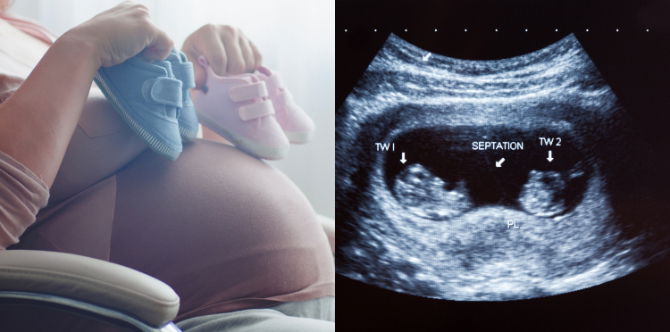

#1. Adakah anak kembar berkongsi plasenta dan kantung amniotik?

Walaupun sesetengah bayi kembar mungkin berkongsi plasenta dan kantung amniotik, itu tidak berlaku untuk kebanyakan kehamilan. Berikut adalah tiga kemungkinan besar yang wujud:

- Dua plasenta dan dua kantung amniotik. Kehamilan kembar dengan dua plasenta dan dua kantung amniotik adalah kehamilan kembar yang optimum, kerana setiap bayi mempunyai sumber pemakanan dan membran pelindungnya sendiri.

- Satu plasenta dan dua kantung amniotik. Dalam kehamilan dengan satu plasenta dan dua kantung amniotik, anda cenderung memiliki kembar seiras. Selain itu, apabila bayi anda berkongsi plasenta, terdapat risiko yang lebih besar untuk komplikasi, seperti sindrom transfusi kembar-ke-kembar. Doktor anda akan memantau kehamilan dengan teliti untuk mengelakkan sebarang masalah.

- Satu plasenta dan satu kantung amniotik. Ini adalah jenis kehamilan kembar yang paling berisiko dan jarang berlaku. Komplikasi janin boleh timbul akibat gangguan tali pusat atau ketidakseimbangan dalam nutrien, darah atau sistem sokongan hidup penting yang lain.